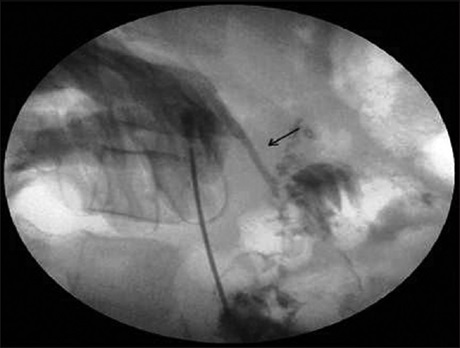

Transarterial Embolization of Nonvariceal Gastrointestinal Bleeding: Our Experience

Dr. Sheo Kumar, Basant Kumar, Archana Gupta, Laxmi Kant Bharti, Anuj Thakral (Author)

56-60